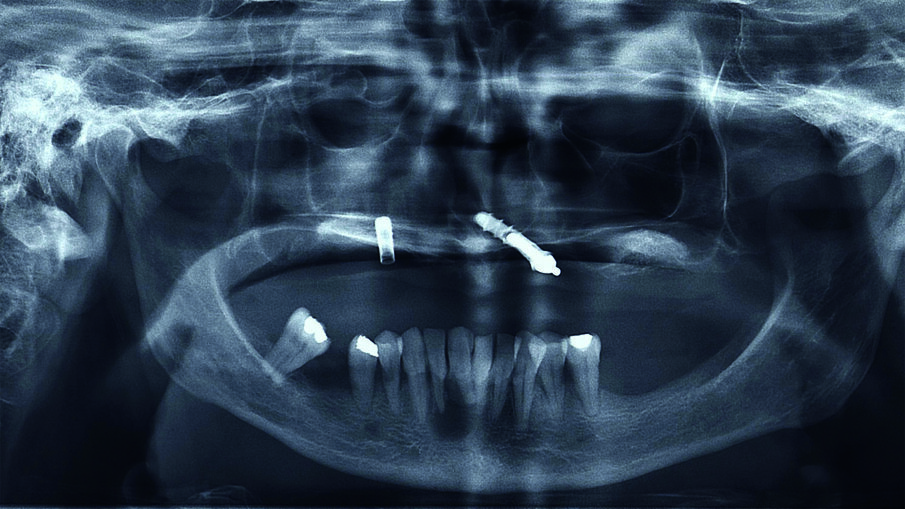

L’esame radiografico mostrava la persistenza di due impianti nel mascellare superiore (Fig. 1) uno dei quali pescava nella cavità nasale. Si osservava inoltre una lesione cistica in regione 4.1-4.2. Il trattamento dell’edentulia totale non può prescindere da una accurata analisi estetica che si concretizzerà in un’analisi Facciale, Dento-Labiale, Fonetica e Dentale. La paziente non mostrava esposizione dentale a riposo e presentava una linea del sorriso inversa (concava e non parallela al labbro inferiore) (Fig. 2). L’analisi del profilo della paziente confermava la necessità di fornire un adeguato supporto dei tessuti peri-orali nel mascellare superiore (Fig. 3). L’esame intra-orale permetteva di apprezzare l’insufficienza dell’estensione della protesi superiore, e la compromissione degli elementi dell’arcata inferiore. All’esame clinico i due impianti mostravano perdita dell’integrazione. (Figg. 4, 5).